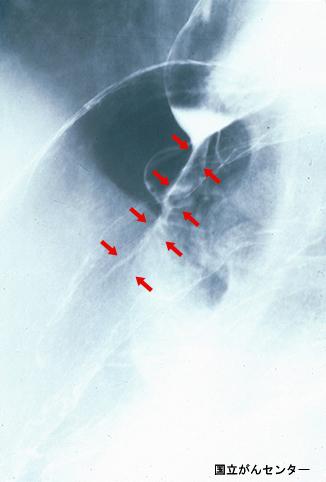

利用X线影像诊断出的马-韦二氏综合征(贲门粘膜裂伤综合征)

Tokyo Pref., 国立癌中心中央病院和九州癌中心共同完成

炎症性・溃疡性疾患/韦二氏综合征(贲门粘膜裂伤综合征)

X线

30~34